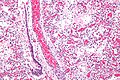

Hyaline membranes. H&E stain. | |

| LM | dependent on phase - exudative: hyaline membranes; proliferative: interstitial thickening, inflammation (lymphocytes), type 2 pneumocyte hyperplasia, edema, Masson bodies in the airway, hyaline material (usu. focal); fibrotic: interstitial inflammation, interstitial fibrosis |

- Exudative:

- Hyaline membranes - key feature.

- Debris (pink crap) lines the alveolar spaces.